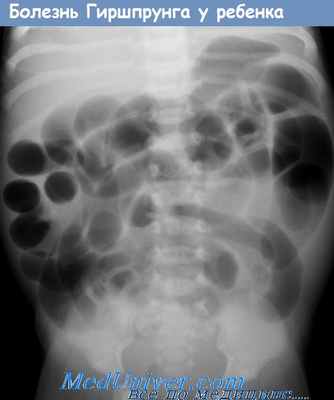

• Рентгенография органов брюшной полости? Дилатация тонкой кишки?

а - Обзорная рентгенограмма брюшной полости взрослого с недавно диагностированной болезнью Гиршспрунга.

Прямая кишка (показана стрелкой) значительно расширена.

б - Зона перехода расширенной нормальной кишки к нерасширенному аганглионарному участку.

Боковой рентгеновский снимок с использованием контраста.